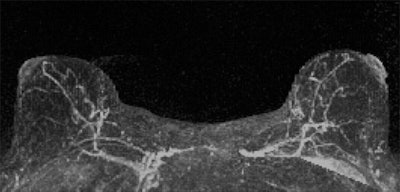

Researchers from the University of Washington found that women with an MRI assessment of mild, moderate, or marked background parenchymal enhancement (BPE) were nine times more likely to develop breast cancer than women with minimal BPE. In contrast, tissue density measured by both MR and mammography was not a statistically significant indicator.

BPE, however, was significantly linked to cancer: The women with mild, moderate, or marked background parenchymal enhancement made up the majority of the cancer cohort.

"We found that a significantly higher percentage of women in the cancer cohort had either mild, moderate, or marked BPE (78%) than did women in the control cohort (43%)," the authors wrote.